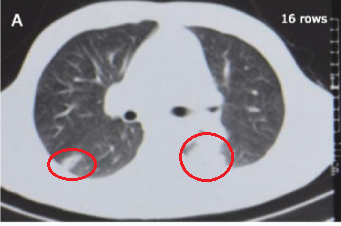

(第一次胸部CT)

当地医院医生把他收入院,前后住了几次院了,做了很多检查,包括胸部CT,最初他被诊断为肺炎,但经过抗感染治疗后病情没有明显好转。

这就奇怪了,青年男性咳嗽、发热、胸痛,最常见的疾病就是肺炎,一般情况下用几次抗生素下去肺炎多数能压的下来,很快就会好转,但这个病人的情况没那么简单。

眼前这个年轻的患者,反复咳嗽、咳痰、胸痛、发热,显然不是普通的肺炎了。

第一次没找到,于是留了第二次痰,第三次,第四次,多留几次痰,肯定能找到抗酸杆菌,毕竟患者的胸部CT看起来那么像肺结核,而且也有长期反复的发热、咳嗽、咳痰、胸痛,必须得是肺结核啊。

当初医生为什么误诊为肺结核呢?除了症状像,更重要的是胸部CT表现也像。我们说原发型肺结核的X线胸片表现为哑铃型阴影,哑铃大家见过吧?就是原发病灶、肿大的肺门淋巴结这两个看起来像哑铃的两端,而中间的引流淋巴管炎像哑铃中间那根铁(手握住的地方),就好像这样:

然后这个患者的表现也是符合的,因为竹签啊,这根竹签模拟了引流淋巴管炎的情况,两端还有脓肿病灶,看起来真的很像原发型肺结核,所以为什么几家医院都会以为是肺结核。